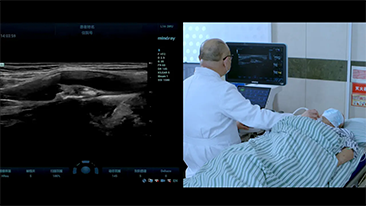

Le soluzioni Mindray Resona per la diagnostica per immagini generale consentono ai medici di ottenere diagnosi e trattamenti con risultati pi├╣ precisi ed efficaci grazie a sonde specifiche complete e a efficienti strumenti clinici applicativi.